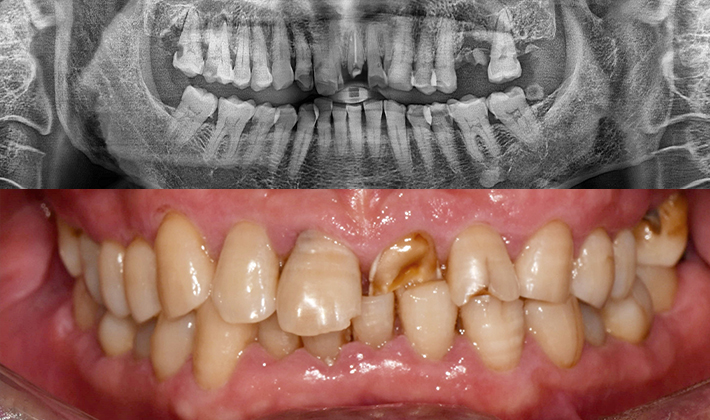

맞는 건 괜찮은데… 충치는 못 참겠습니다|20대 격투기 선수 치과 방문기